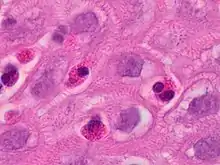

At a tissue level, EoE is characterized by a dense infiltrate with white blood cells of the eosinophil type into the epithelial lining of the esophagus. This is thought to be an allergic reaction against ingested food, based on the important role eosinophils play in allergic reactions. The eosinophils are recruited into the tissue in response to local production of eotaxin-3 by IL-13 stimulated esophageal epithelial cells.[3]

Endoscopically, ridges, furrows, or rings may be seen in the esophageal wall. Sometimes, multiple rings may occur in the esophagus, leading to the term "corrugated esophagus" or "feline esophagus" due to similarity of the rings to the cat esophagus. Presence of white exudates in esophagus is also suggestive of the diagnosis.[13] On biopsy taken at the time of endoscopy, numerous eosinophils can be seen in the superficial epithelium. A minimum of 15 eosinophils per high-power field are required to make the diagnosis. Eosinophilic inflammation is not limited to the esophagus alone, and does extend through the whole gastrointestinal tract. Profoundly degranulated eosinophils may also be present, as may micro-abscesses and an expansion of the basal layer.[3][10]

Endoscopic mucosal biopsy remains the gold standard diagnostic test for EoE, and is required to confirm the diagnosis.[8] Endoscopy with biopsies of the esophagus has a 100% sensitivity and 96% specificity for the diagnosis of eosinophilic esophagitis.[8] Biopsy specimens from both the proximal/mid and distal esophagus should be obtained regardless of the gross appearance of the mucosa. Specimens should also be obtained from areas revealing endoscopic abnormalities.[2] 2-4 biopsies should be obtained from both the proximal and distal esophagus to obtain adequate tissue samples for the detection of EoE.[2] A definitive diagnosis of EoE is based on the presence of at least 15 eosinophils/HPF in the esophageal biopsies of patients with exclusion of other causes of eosinophilia in the esophagus including gastroesophageal reflux disease (GERD), achalasia hypereosinophilic syndrome, Crohn's disease, infections, pill esophagitis, or graft vs host disease.[8] Endoscopy is usually indicated after treatment is started for EoE to confirm histologic remission.[8]